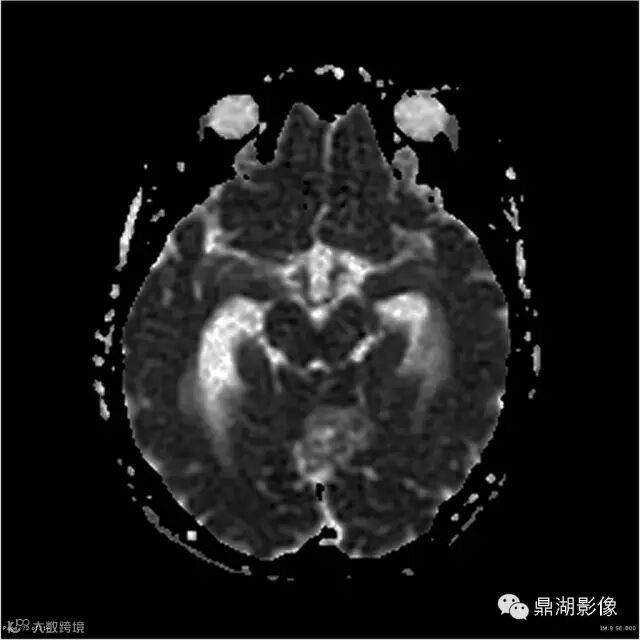

Axial DWI

本例为一例实质性血管母细胞瘤。实性血管母细胞瘤CT平扫示病灶呈等或高密度,增强后可见明显强化。MRI平扫通常病灶很不均质,T1呈稍低信号为主的较混杂信号,T2呈等、高信号,DWI通常呈低信号或等信号。文献报道,实性血管母细胞瘤较典型的表现为瘤内及瘤周扩张的流空血管影,瘤周中、重度水肿。因此,小脑半球区的单发肿块伴流空血管影,周围大片水肿以及增强后肿块明显强化"形态规则"边界清楚,此时应将实性血管母细胞瘤考虑在内。

实性血管母细胞瘤须与脑膜瘤、淋巴瘤、室管膜瘤等鉴别;脑膜瘤,为脑外肿瘤,极少发生囊变,多数可见“脑膜尾征”,出血及坏死少见,瘤周水肿较轻;淋巴瘤,常位于深部脑组织,无血管流空影,DWI上呈高信号,文献报道,实性血管母细胞瘤 DWI( b=1000) 呈低信号有助于两者鉴别;室管膜瘤一般瘤周无蚓状流空的肿瘤供血动脉,增强时强化程度不及血管母细胞瘤。